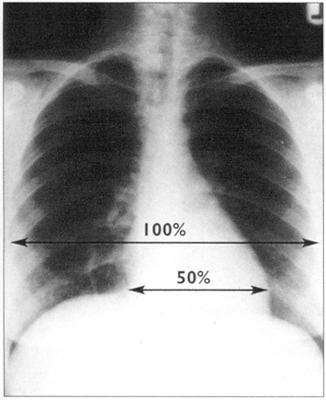

心胸比率能说明心脏大小。算法为心影的最大横径除以胸腔的最大横径,心胸比率只能在后前位上计算。正常情况下,其值应小于50%。左室和右房增大通常很容易鉴别,左房增大好像心缘又多出一个影,即双房影。